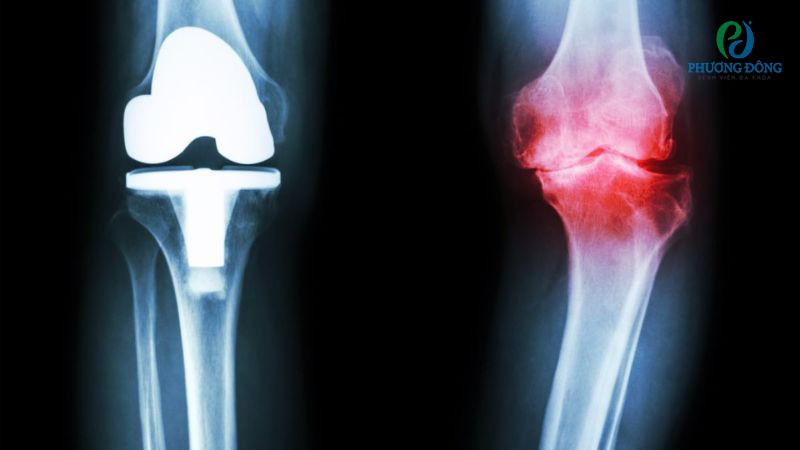

Thoái hóa khớp gối là tình trạng sụn khớp bị bào mòn, mất khả năng bảo vệ hai đầu xương dẫn đến đau nhức, cứng khớp và hạn chế vận động. Bệnh bắt đầu tiến triển từ ngoài 30 tuổi, nhưng thực sự rõ rệt sau tuổi 55, do quá trình lão hóa tự nhiên và ảnh hưởng bởi thói quen sinh hoạt.

Ngồi xuống đứng lên đau đầu gối là triệu chứng sớm của bệnh, sụn khớp khi này mất độ trơn láng khiến hai đầu xương trực tiếp cọ xát với nhau và gây đau. Về lâu dài, nếu không được can thiệp sớm đầu gối có thể bị biến dạng nhẹ, sưng nề và mất khả năng chịu lực.

Ngồi xuống đứng lên bị đau đầu gối là triệu chứng sớm của thoái hóa khớp

Bệnh không có khả năng điều trị hoàn toàn, người bệnh chỉ có thể làm chậm quá trình tiến triển bằng cách giữ cân nặng ổn định, tập luyện nhẹ nhàng và dùng thuốc. Với trường hợp thoái hóa nặng, can thiệp ngoại khoa như tiêm huyết tương giàu tiểu cầu, thay khớp gối sẽ được chỉ định.